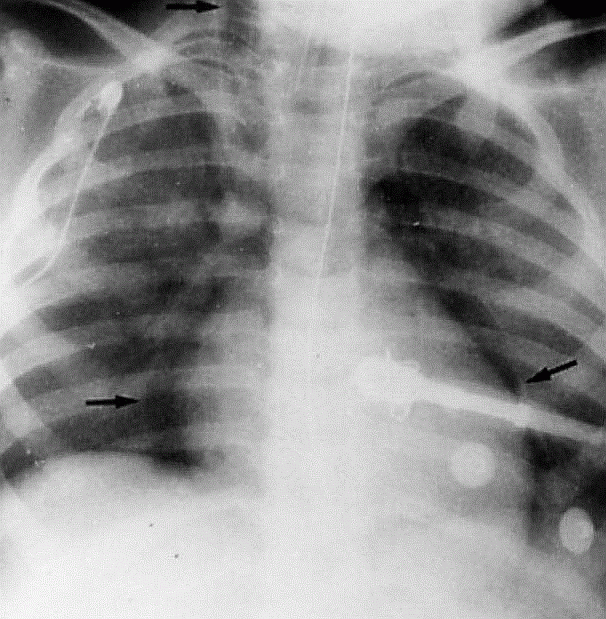

Sepsisli xəstələrdə rentgenoloji müayinədə mediastinumda hava görünməsi yüksək şübhə əlamətidir (Şəkil 9).

Şəkil 9. Mediastinal emfizema